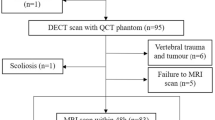

First, a real-time phantom consisting of oil and water tubes was manufactured. Then, 30 female volunteers (age: 62.3 ± 6.3 years) underwent lumbar spine examination with MRI (using a novel phantom) and dual-energy X-ray absorptiometry (DXA), following ethical approval. MRI phantom-based F-score and W-score were defined by normalizing the vertebral signal intensities (SIs) by the oil and water SIs of the phantom on T1- and T2-weighted images, respectively. The diagnostic performances of the new scores for assessing osteoporosis and vertebral fractures were examined using receiver operating characteristic analysis and compared with DXA-measured areal bone mineral density (DXA-aBMD).